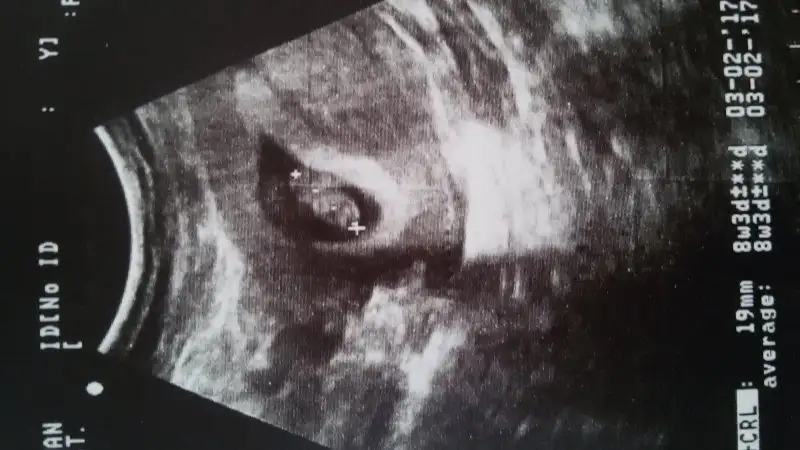

6. Hafta , 7. Hafta (ikisi de vaginal) ve 11+5 haftalık usg